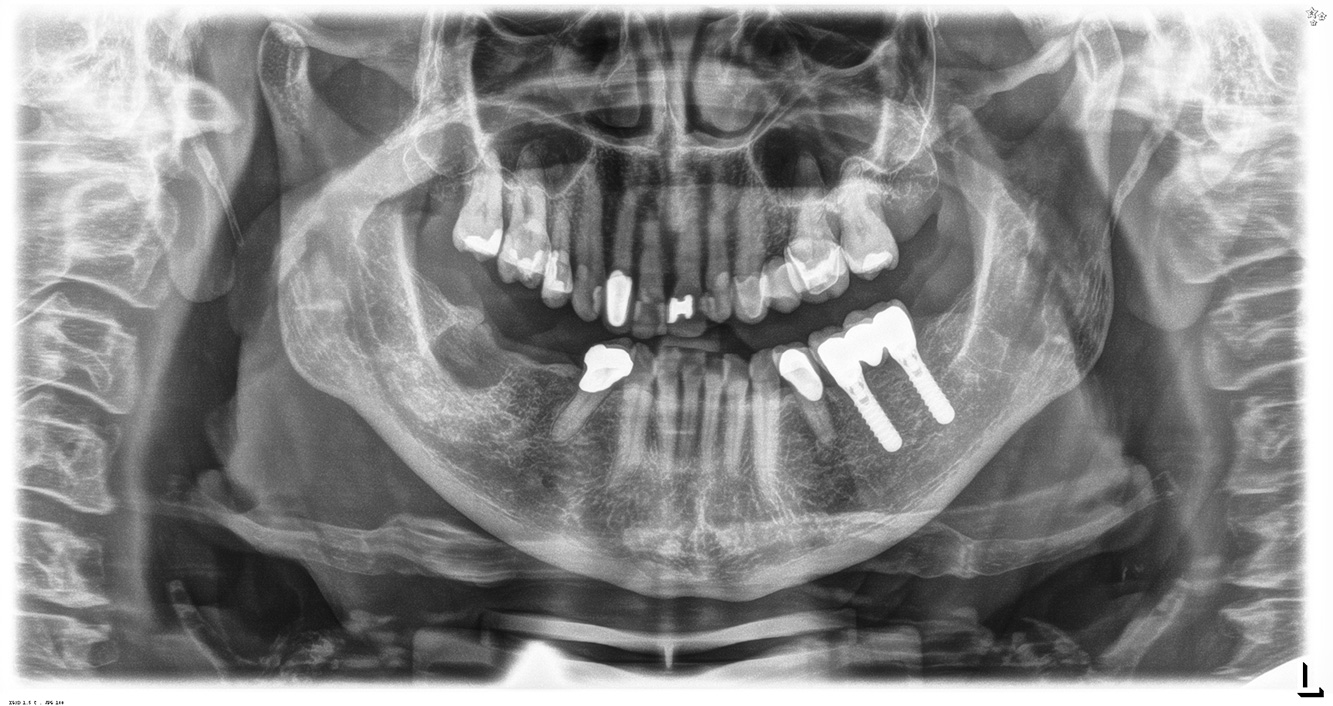

The (orally) healthy patient with implants

In the medical history, the 55-year-old patient states that he has no systemic disease and is not taking any medication. The patient’s lifestyle is similarly unremarkable. The patient has a few tooth restorations and two implants (2nd and 4th quadrants). On the basis of current findings, gingivitis is identified in an otherwise stable periodontal condition on the reduced periodontium (stage III, grade A). more

Pacient sănătos cu boală parodontală incipientă

Pacientul în vârstă de 68 de ani nu are nicio afecțiune generală și nu ia niciun medicament care ar putea fi relevant pentru sănătatea sa orală, iar stilul său de viață nu prezintă niciun risc special. Pacientul are două implanturi dentare (cadranul 3, de cinci ani) și un caz anterior de boală parodontală (stadiul IV, gradul B) cu pierderea dinților. În prezent, condițiile parodontale sunt stabile. Cu toate acestea, parodontoza crește semnificativ complicațiile biologice ale implanturilor și există riscul de pierdere a implanturilor (21). Se pot determina patru recomandări pentru ședința de profilaxie. mai multe